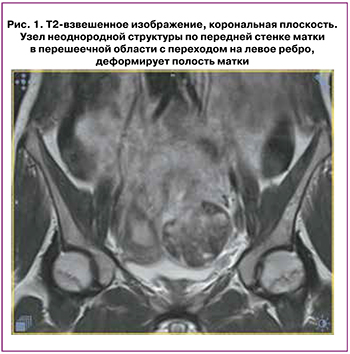

Магнитно-резонансная томография (МРТ) малого таза: матка в антефлексио, антеверзио. Не смещена. Контуры ее четкие, неровные. Тело матки размерами 64×60×72 мм. Полость матки шириной до 7 мм, с незначительным количеством геморрагического содержимого. По передней стенке матки с переходом на левое ребро, в перешеечной области (выполняя стенку матки, деформируя полость и наружный контур) определяется крупный узел неоднородной структуры размерами 75×60×65 мм, распространяется на переднюю стенку шейки матки, деформирует полость (рис. 1). Структура узла неоднородная, имеет геморрагическое пропитывание, со стороны полости контуры узла неровные, с дефектами на глубину до 2 см и более, выраженным отеком по периферии данных изменений.

Заключение. Рубец на матке после кесарева сечения. Узловое образование в проекции рубца после кесарева сечения (возможно, узел миомы с признаками повреждения в ходе выскабливания).